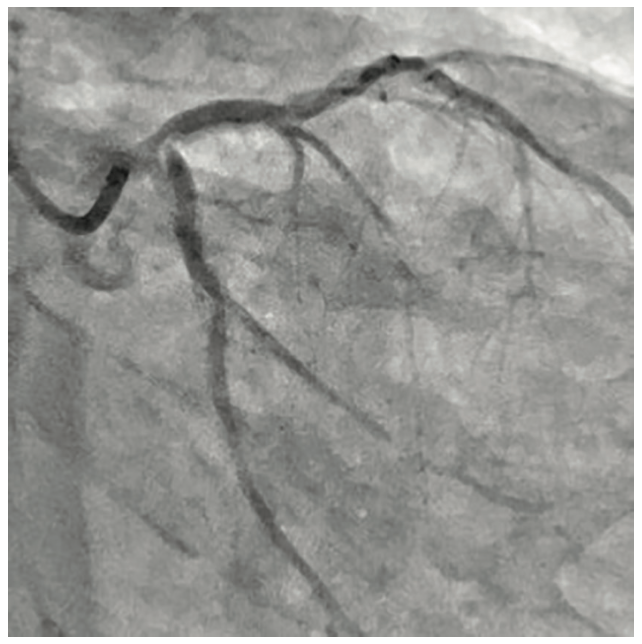

Right radial access was obtained with a radial 7 French (Fr), 10 cm length GLIDESHEATH SLENDER® Introducer Sheath (Terumo Interventional Systems) and the ostium of the LMCA was engaged with a 7 Fr Extra Backup (EBU) 3.5 guide catheter (Medtronic) to facilitate bifurcation stenting. The initial angiogram images revealed a worsening of the distal LMCA stenosis, now at 80% and extending into the ostial LAD (Figure 1). A Runthrough NS Izanai White guidewire was advanced across the lesion into the distal LAD and a Runthrough NS Izanai Blue was advanced across the lesion into the distal LCx with minimal difficulty. To facilitate intravascular ultrasound catheter delivery, the distal LMCA/ostial LCx was predilated with a semicompliant 2.0 mm x 15 mm Takeru PTCA Balloon Dilatation Catheter at nominal pressure (8 atmospheres). IVUS of the LCx was performed first, followed by IVUS of the LAD, and showed severe, concentric calcification of the distal LMCA and ostial LAD/LCx (Figure 2). For plaque modification and lesion optimization prior to stent deployment, a 3.5 mm x 12 mm C2+ intravascular lithotripsy balloon (IVL, Shockwave Medical) was advanced first into the LCx and subsequently into the LAD. The LMCA to proximal LCx and the ostial LAD were treated with 120 pulses with 12 inflations of the IVL balloon. Angiography revealed no evidence of dissection following IVL; however, there was some recoil in the ostial LCx, for which cutting balloon angioplasty was performed with a 3.5 mm x 15 mm Wolverine balloon (Boston Scientific) in the ostial LCx and extending back into the distal left main. Next, the decision was made to proceed with bifurcation stenting using a culotte strategy. A 3.5 mm x 20 mm Synergy Megatron drug-eluting stent (DES, Boston Scientific) was placed from the distal LMCA into the proximal LCx (Figure 3). Following post dilation of the DES with a 3.5 mm x 15 mm noncompliant balloon, a new Runthrough NS Izanai White was used to re-wire the LAD through a side strut of the LMCA-LCx DES. A semicompliant 3.0 mm x 12 mm Takeru PTCA Balloon Dilatation Catheter crossed into the LAD with minimal difficulty and was used to dilate the stent struts to facilitate delivery of the LMCA-LAD DES. A noncompliant 3.0 mm x 15 mm balloon inflation was performed to optimize the LAD lesion further. A 3.5 mm x 16 mm Synergy Megatron DES was then placed in the proximal LAD, overlapping with the prior stent in the LMCA (Figure 4). Following post dilation of the LMCA-LAD DES with a 3.5 mm x 15 mm noncompliant balloon, the proximal portion was optimized (proximal optimization technique [POT]) with a 4.0 mm x 8 mm noncompliant balloon. The LCx was then rewired with the Runthrough NS Izanai White through a side strut of the LMCA-LAD stent and the Runthrough NS Izanai Blue was placed in the LAD. Following serial dilations of the LMCA-LAD stent struts with Takeru PTCA Balloon Dilatation Catheters, kissing balloon inflation of both the LAD and LCx extending back into the LMCA was performed with a 3.5 mm x 15 mm noncompliant balloon in the LCx and a 3.0 mm x 15 mm noncompliant balloon in the LAD (Figure 5). Repeat IVUS of both stents back into the LMCA was performed, demonstrating adequately expanded and apposed stents with no evidence of edge dissection. Final POT was performed in the LMCA with a 4.5 mm x 8 mm noncompliant balloon. Final angiography revealed TIMI-III flow, no evidence of proximal or distal edge dissections, no perforation, and <5% residual stenosis (Figure 6). The total contrast volume was 55 mL with a case length of 1.5 hours. The patient was discharged three days later without complication.